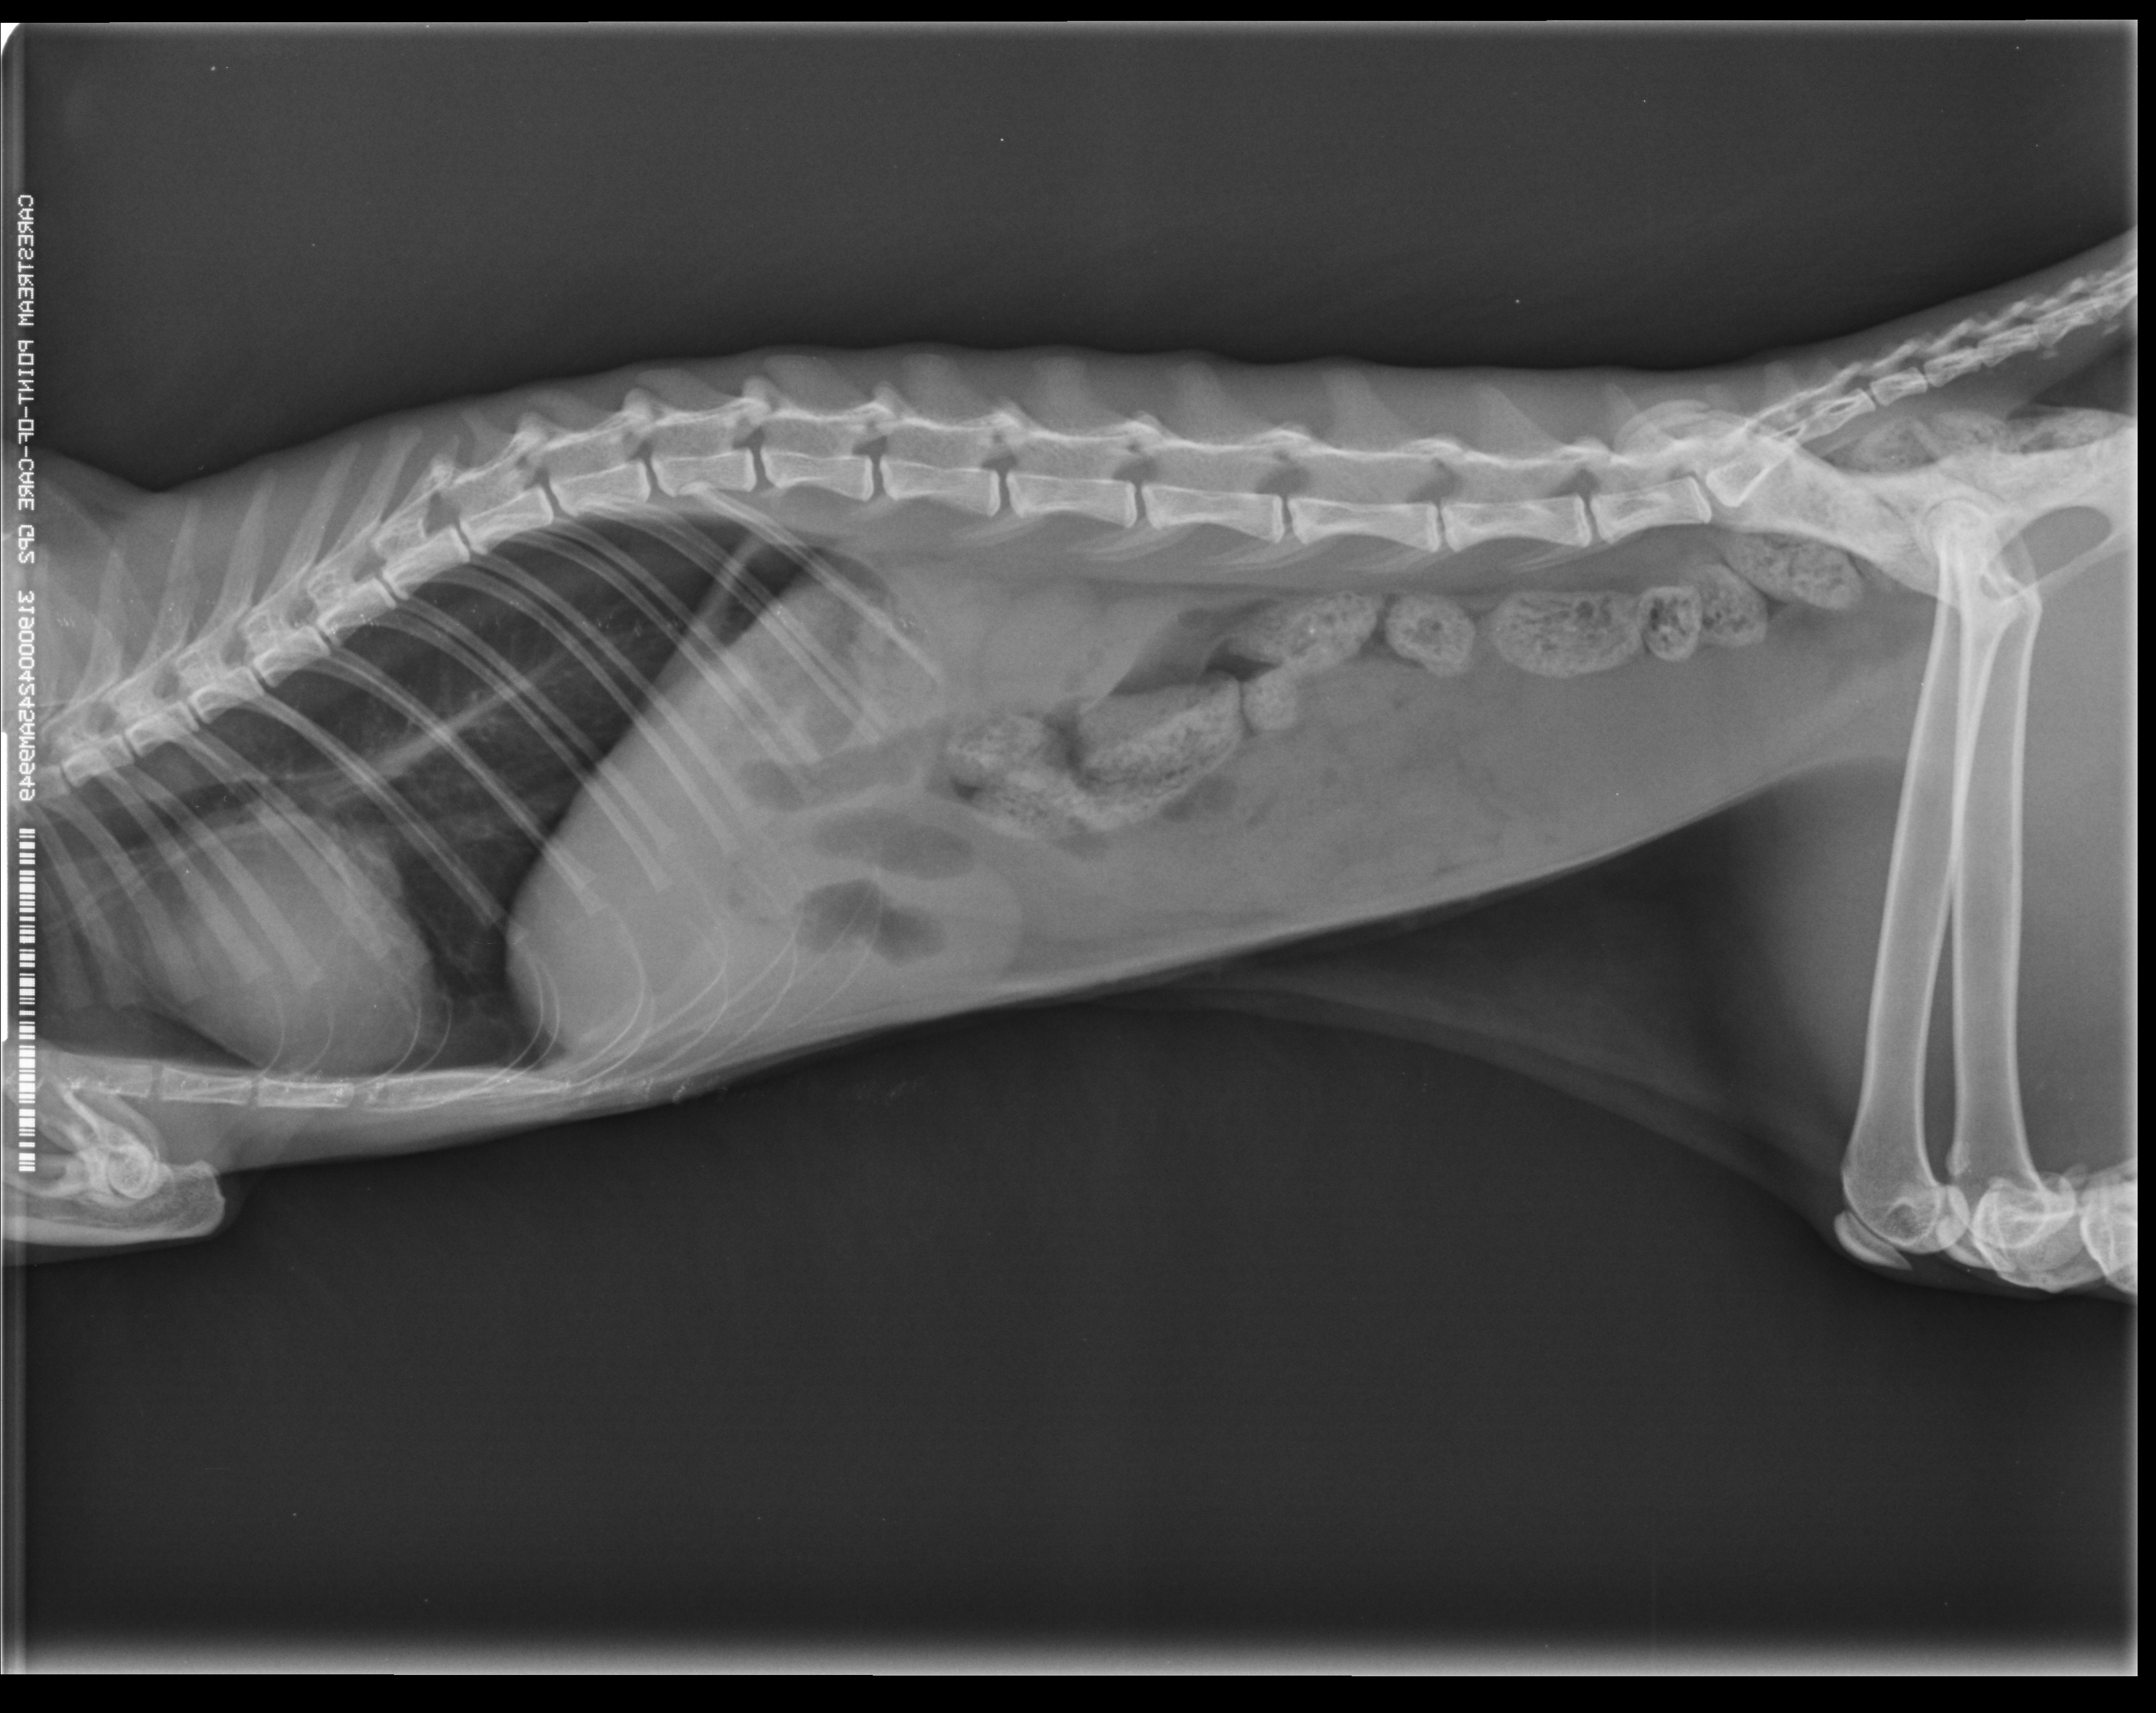

Treatment: Surgical removal of the foreign body(pic4).

Ακτινογραφία πριν τον υπέρηχο(Xray made prior to the U/S)

Αντιμετώπιση: Έγινε χειρουργική αφαίρεση του ξένου σώματος(pic4).